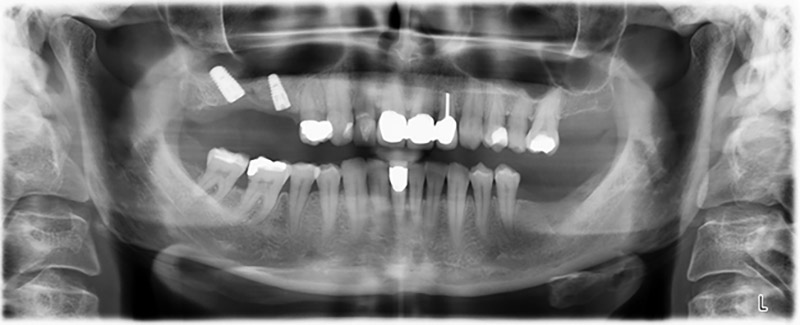

The 59-year-old patient presented with an advanced case of periodontitis, describing an unpleasant feeling and poor taste from the first quadrant in a distal direction. The clinical examination revealed generally enlarged periodontal pockets and very advanced bone atrophy in regions 16 and 14. The radiology confirmed the findings (Fig. 1). Teeth 16 and 14 could not be retained.